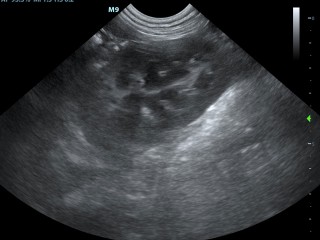

Echografie buik

Met een echo onderzoek kunnen we goed de organen bekijken. We bekijken en beoordelen het orgaan naar grootte, vorm en inhoud. Je kunt alle organen goed onderzoeken. Voor het beoordelen van de maag is het belangrijk dat het dier nuchter komt. Om de wand van de urineblaas goed te kunnen beoordelen moet de blaas gevuld zijn.

De organen die we routinematig beoordelen zijn:

Blaas - Prostaat - Baarmoeder/eierstokken - Lymfeklieren - Darmen - Nieren - Bijnieren - Milt - Alvleesklier - Maag - Lever

De buik in beeld

Hieronder zie je een aantal foto's van de buik met achtereenvolgens; blaasontsteking, blaastumor, vroege dracht hond 19 dagen, vergrote eierstok, lever, nier.